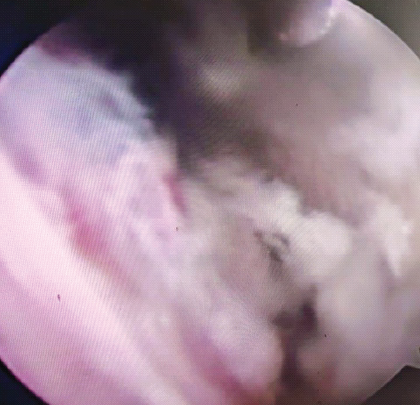

Comparative Efficacy of Manipulation Under Anaesthesia Versus Arthroscopic Capsular Release in Primary Frozen Shoulder: A Prospective Randomized Study

Atanu Mohanty , Anuraag Mohanty

………………………………p.414-421